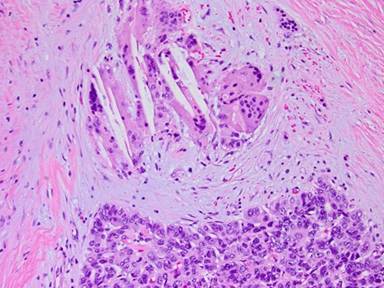

Following a visit to the University of Colorado Multidisciplinary Gastro-Intestinal Tumor Clinic, the patient underwent neo-adjuvant chemotherapy with 3 months of FOLFIRINOX followed by restaging. Repeat pancreas protocol CT scan showed a decrease in the size of the entire pancreas with both masses (head and tail) also decreasing in size. A total pancreatectomy was offered and performed (Figure 3). Segmental superior mesenteric vein resection was also done with an end to end anastomosis, as the tumor came within less than 1 millimeter from the retroperitoneal margin on frozen section. The postoperative course was uncomplicated and the patient was discharged home on day 7. The final pathology demonstrated two discrete tumor masses, 5.0 cm and 4.5 cm, with extensive colonization of the intervening pancreatic duct. On histology, the tumor consisted of sheets of undifferentiated carcinoma cells separated by dense fibrosis. Clusters of multinucleated foreign body-type giant cells, associated with cholesterol clefts and other degenerative features, were present in the stroma adjacent to the tumor cells. These were interpreted as neoadjuvant treatment effect and not as native component of the tumor (Figure 4). All margins, including the superior mesenteric vein segment, were negative for malignancy; three of 28 lymph nodes contained metastatic deposits. Immunohistochemical staining was positive for pancytokeratin AE1:AE3, CA 19-9 and patchy positive for B72.3, negative for chromogranin and synaptophysin and equivocal for CEA. Final pathologic staging was pT3N1M0.

Figure 4. Foreign body giant cells. |